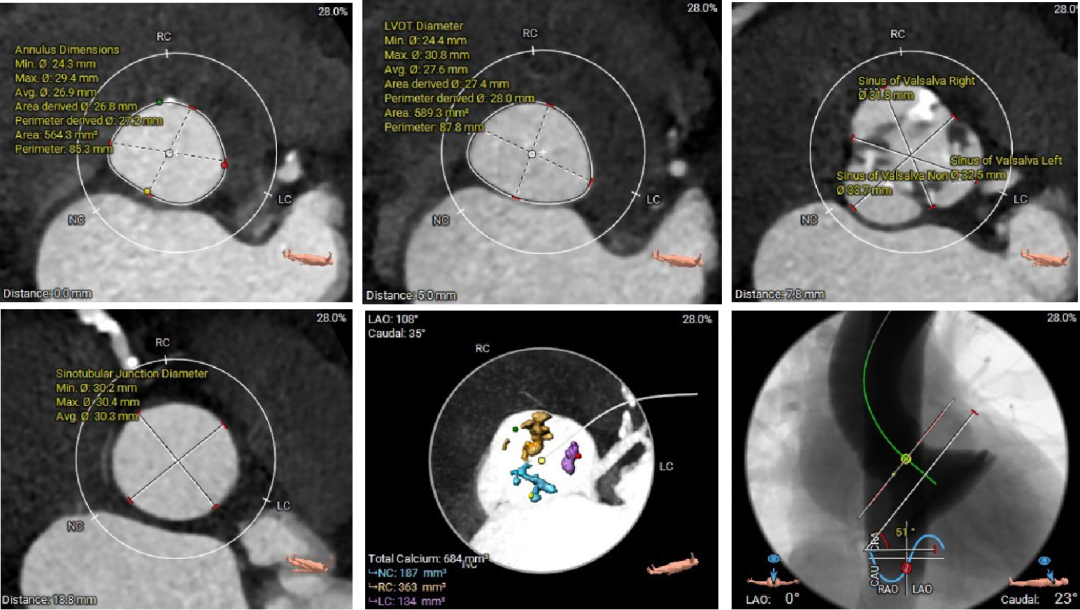

范嘉祺教授就CT在TAVR术前评估及手术策略制定展开了深入讲解。TAVR术前CT评估主要包括:1、入路血管的评估选择入路方式;2、主动脉根部解剖的评估制定球囊、瓣膜选择策略;3、心室大小、冠状动脉阻挡风险等。4、相比西方国家,我国二叶瓣比较高,且产生严重钙化的比例也较高,以往根据瓣环选择瓣膜的策略可能带来风险。故针对国内患者的情况,需要术前更加精细的瓣上结构分析,并结合术中球扩,优化瓣膜选择策略,提高手术的安全性和有效性。

精彩的理论授课外,王建安教授团队通过一例复杂的TAVR手术演示,全面展示了Hangzhou Solution在评估瓣上结构,指导二叶瓣TAVR手术策略的应用,以及可回收系统在复杂病变中给临床带来的获益。

患者CT

根部瓣上

根部VR

主动脉根部

冠脉及心室